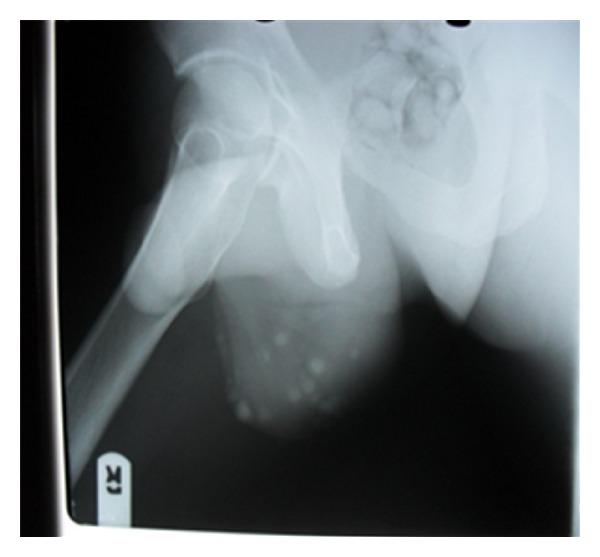

Idiopathic scrotal calcinosis is an uncommon benign disorder of the scrotal skin which is characterized by multiple calcified intradermal nodules. We report a 33-year old with asymptomatic multiple calcified scrotal skin nodules. He had wide excision of the lesions and direct closure of the scrotum. We review the pathogenesis and surgical treatment options for this rare disease of the scrotum.

特发性阴囊钙化症是一种罕见的阴囊皮肤良性疾病,其特征为多个真皮内钙化结节。我们报告一例33岁男性,有无症状的多个阴囊皮肤钙化结节。他接受了病变广泛切除及阴囊直接缝合。我们回顾了这种罕见阴囊疾病的发病机制及手术治疗选择。